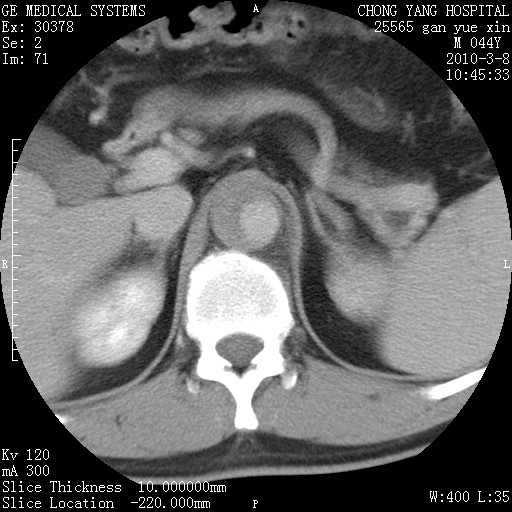

标题: CT24940:主动脉增强,典型病例。 [打印本页]

标题: CT24940:主动脉增强,典型病例。

夹层动脉瘤。

动脉夹层

夹层动脉瘤,典型

主动脉夹层。

动脉夹层的分型:

⒈debakey分型:根据主动脉夹层累及部位,分为三型:ⅰ型:原发破口位于升主动脉或主动脉弓部,夹层累及升主动脉、主动脉弓部、胸主动脉、腹主动脉大部或全部,少数可累及髂动脉。ⅱ型:原发破口位于升主动脉,夹层累及升主动脉,少数可累及部分主动脉弓。ⅲ型:原发破口位于左锁骨下动脉开口远端,根据夹层累及范围又分为ⅲa,ⅲb。ⅲa型:夹层累及胸主动脉。ⅲb型:夹层累及升主动脉、腹主动脉大部或全部。少数可累及髂动脉。

⒉stanford分型:a型:夹层累及升主动脉,无论远端范围如何。b型:夹层累及左锁骨下动脉开口以远的降主动脉。

夹层动脉瘤,少量胸水

夹层动脉瘤;左侧少量胸腔积液。

典型主动脉夹层。